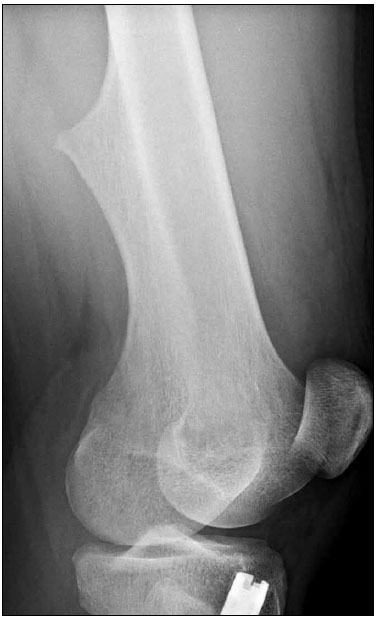

William Yaakob, MD; Roli Agrawal, MD; Sarah Kizilbash, MD

<p><img src="/sites/default/files/transfer/Untitled-48_0.jpg" style="margin-left: 8px; margin-right: 8px; float: left;" width="150" height="246">An...